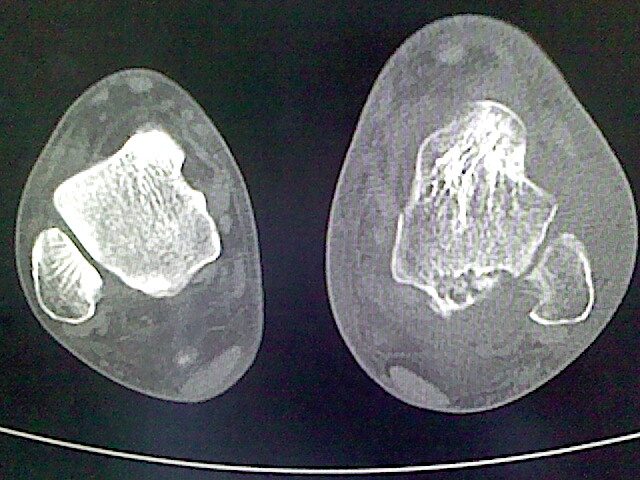

标题: CT16814:男,76岁,左小腿疼痛,不能站立 大家给看看 [打印本页]

男,76岁,左小腿疼痛,不能站立

本例骨质改变主要表现为滑膜或韧带区的骨侵蚀融解(胫腓联合区骨质破坏无硬化边),距骨后部骨质破坏区有硬化边及死骨样改变.所以,本例考虑关节结核可能性大,绒毛膜结节性滑膜炎多发于中年,且极少见于膝髋以外的关节,骨质硬坏也以压陷吸收为主,有明显的硬化边,骨膜增生呈结节状(可以mr鉴别),所以本例暂除外.

另不除外可引起相似表现的其他炎症如布氏杆菌性关节炎等